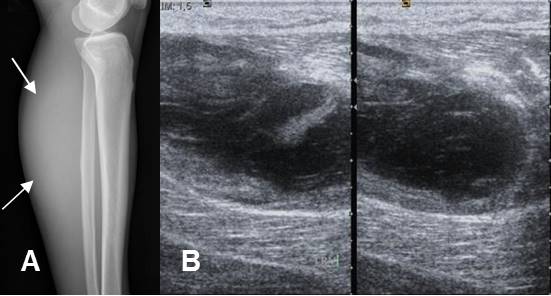

Fig 149. Hematoma muscular.

A: Rx lateral. Prominencia en los tejidos blandos de la región posterior.

B: Ecografía axial. Colección líquida dentro del músculo gemelo, por hematoma.